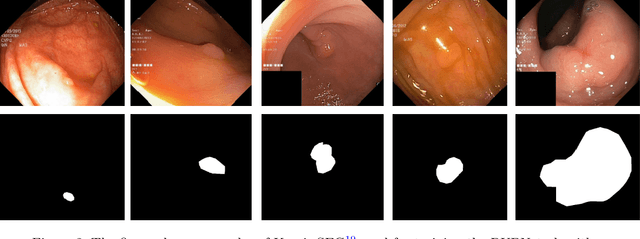

RUPNet: Residual upsampling network for real-time polyp segmentation

Colorectal cancer is among the most prevalent cause of cancer-related mortality worldwide. Detection and removal of polyps at an early stage can help reduce mortality and even help in spreading over adjacent organs. Early polyp detection could save the lives of millions of patients over the world as well as reduce the clinical burden. However, the detection polyp rate varies significantly among endoscopists. There is numerous deep learning-based method proposed, however, most of the studies improve accuracy. Here, we propose a novel architecture, Residual Upsampling Network (RUPNet) for colon polyp segmentation that can process in real-time and show high recall and precision. The proposed architecture, RUPNet, is an encoder-decoder network that consists of three encoders, three decoder blocks, and some additional upsampling blocks at the end of the network. With an image size of $512 \times 512$, the proposed method achieves an excellent real-time operation speed of 152.60 frames per second with an average dice coefficient of 0.7658, mean intersection of union of 0.6553, sensitivity of 0.8049, precision of 0.7995, and F2-score of 0.9361. The results suggest that RUPNet can give real-time feedback while retaining high accuracy indicating a good benchmark for early polyp detection.